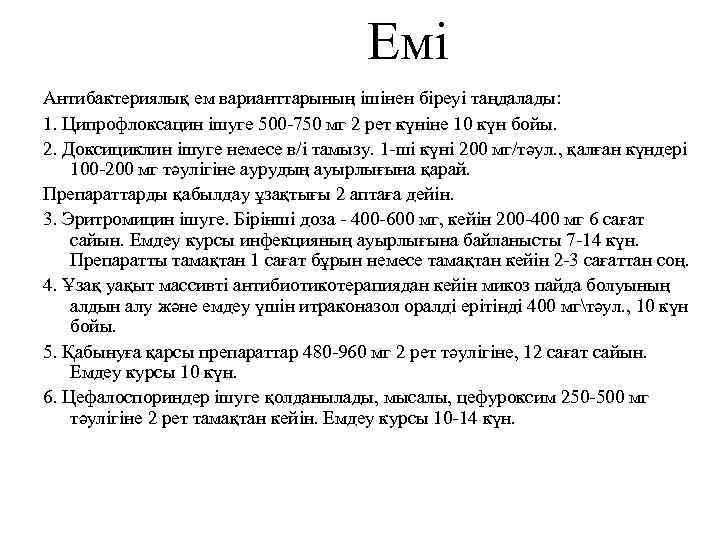

Емі Антибактериялық ем варианттарының ішінен біреуі таңдалады: 1. Ципрофлоксацин ішуге 500 -750 мг 2 рет күніне 10 күн бойы. 2. Доксициклин ішуге немесе в/і тамызу. 1 -ші күні 200 мг/тәул. , қалған күндері 100 -200 мг тәулігіне аурудың ауырлығына қарай. Препараттарды қабылдау ұзақтығы 2 аптаға дейін. 3. Эритромицин ішуге. Бірінші доза - 400 -600 мг, кейін 200 -400 мг 6 сағат сайын. Емдеу курсы инфекцияның ауырлығына байланысты 7 -14 күн. Препаратты тамақтан 1 сағат бұрын немесе тамақтан кейін 2 -3 сағаттан соң. 4. Ұзақ уақыт массивті антибиотикотерапиядан кейін микоз пайда болуының алдын алу және емдеу үшін итраконазол оралді ерітінді 400 мгтәул. , 10 күн бойы. 5. Қабынуға қарсы препараттар 480 -960 мг 2 рет тәулігіне, 12 сағат сайын. Емдеу курсы 10 күн. 6. Цефалоспориндер ішуге қолданылады, мысалы, цефуроксим 250 -500 мг тәулігіне 2 рет тамақтан кейін. Емдеу курсы 10 -14 күн.